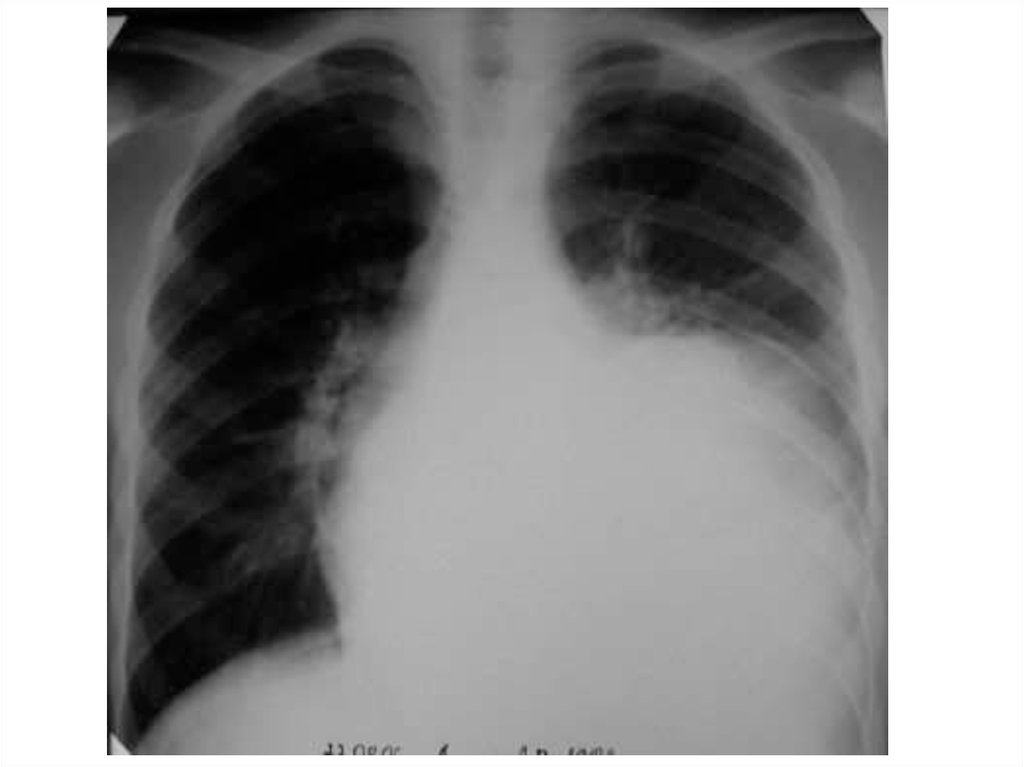

• Среди рентгенологических признаков

повреждений пищевода следует различать

косвенные признаки и прямые.

• Косвенные признаки можно определить при

полипозиционной рентгеноскопии шеи и грудной

клетки, выявленные изменения фиксируются затем

на рентгенограммах. Наиболее распространенным

признаком повреждения пищевода является

наличие эмфиземы околопищеводной

клетчатки шеи и средостения, межфасциальных

пространств шеи, подкожной клетчатки.

Возникновение пневмоторакса,

гидроторакса или гидропневмоторакса также

является косвенными признаками разрыва

пищевода.